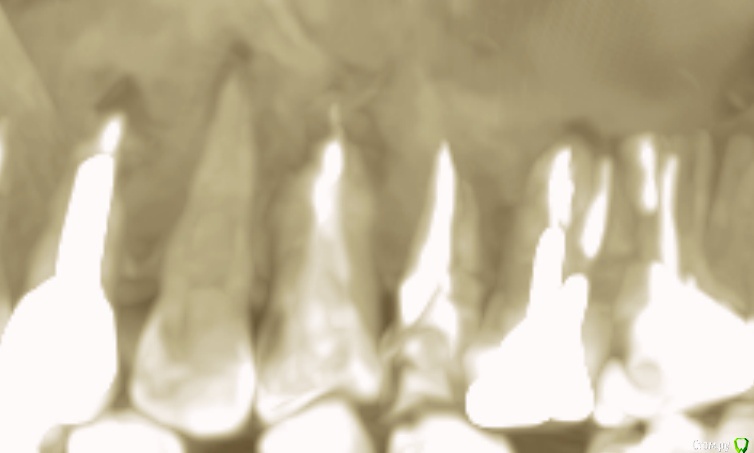

klemento Опубликовано 30 октября, 2019 Автор Поделиться Опубликовано 30 октября, 2019 (изменено) Дело ваше, я свое мнение уже высказал, а снимок на визиографе вы так и не предоставили...ищите эндодонтиста, тот который занимается лечением каналов профессионально.Про снимок твердят не имеет смысла. 26 на снимках в прошлом сообщении, где пятна - это не гранулема/киста/воспаление?Нашел старые за август. Не знаю информативны или нет. На первом 26 и 25. На втором 27 и 26. Изменено 30 октября, 2019 пользователем klemento Ссылка на комментарий

klemento Опубликовано 30 октября, 2019 Автор Поделиться Опубликовано 30 октября, 2019 Вы тогда определитесь кому больше доверяете. Я смотрю 5-6 новых томограмм ежедневно с разными ситуациями, сложными и простыми, а у вас 1 томограф на весь Гомель, опыта работы с томограммами у докторов очень мало, все мои пациенты проходят томографическое исследование, при необходимости я делаю снимки на визиографе, когда это требуется, в вашем случае требуеся. По 10 раз я не буду объяснять, что нужно у меня нет на это времени.Эти не подходят? Ссылка на комментарий

krokomot Опубликовано 30 октября, 2019 Поделиться Опубликовано 30 октября, 2019 Эти не подходят?нет, снимок должен быть выполнен параллельно зубному ряду Ссылка на комментарий